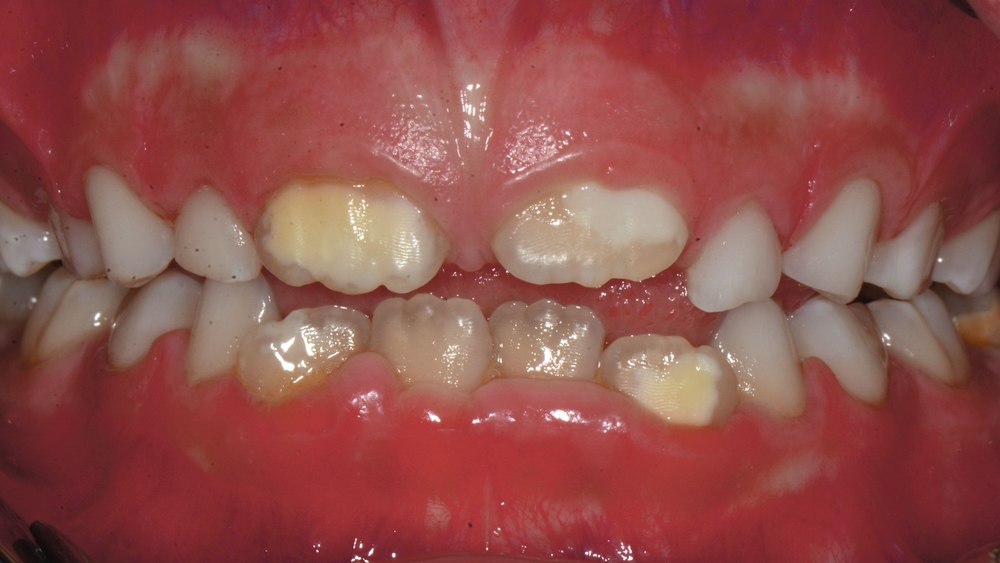

Die MIH (Abbildungen 1 und 2) stellt eine Strukturstörung der Zähne dar, die sich während der Zahnentwicklung manifestiert und daher bereits vor dem Durchbruch des Zahns in die Mundhöhle vorhanden ist. Obwohl der Name suggeriert, dass die ersten bleibenden Molaren und bleibenden Inzisiven die bevorzugten Indexzähne beziehungsweise Zahngruppen in der bleibenden Dentition sind, nutzt die Definition der European Academy of Paediatric Dentistry (EAPD) ausschließlich die ersten bleibenden Molaren zur Diagnosestellung. Entsprechend dieser Vorgabe muss zumindest ein erster bleibender Molar Zeichen einer MIH-bedingten Strukturstörung aufweisen [Lygidakis et al., 2010, 2022], damit die Diagnose einer MIH gestellt werden kann.

Das klinische Erscheinungsbild an bleibenden Zähnen zeigt typischerweise weißlich-gelbe bis gelblich-braune Opazitäten, die zumindest in einigen Bereichen durch eine scharfe Abgrenzung (engl.:„demarcated opacities“) zum gesunden Zahnschmelz charakterisiert sind (Abbildungen 3 und 4). Die abgegrenzten Hypomineralisationen befinden sich mehrheitlich im Bereich der inzisalen Kronenhälfte unabhängig von dem Auftreten an Front- oder Seitenzähnen. Die Ausprägung am Zahn kann dabei auf einzelne Areale oder Höcker begrenzt sein.

Bei einer schwerwiegenderen Ausprägung sind Zahnflächen vollständig betroffen, mitunter alle Zahnflächen an einem Zahn. Die Verteilung in der Dentition beziehungsweise an den Indexzähnen ist gleichermaßen variabel und betrifft nicht nur die Defektgröße, sondern auch die Farbe und Festigkeit. Was die Festigkeit betrifft, gilt als die Faustregel: Je dunkler die Farbe des Schmelzes, umso weicher beziehungsweise poröser und damit minderwertiger wird dessen Qualität sein. Damit reduziert sich seine kaufunktionelle Belastungsfähigkeit, was insbesondere an ersten bleibenden Molaren von klinischer Relevanz ist.

Für die Dokumentation und Klassifikation der MIH wurden verschiedene Systeme vorgeschlagen. Als historisch und veraltet gilt der (modifizierte) DDE-Index. Demgegenüber haben die Kriterien der EAPD – abgegrenzte Opazitäten (Abbildung 3 und 4), Schmelzeinbrüche (Abbildung 5), atypische Restaurationen (Abbildung 6) – mittlerweile die weiteste Verbreitung gefunden. Diese wurden 2003 erstmals zur Beschreibung der MIH auf empirischer Basis publiziert [Weerheijm et al., 2003] und den Jahren 2010 und 2022 im Rahmen der damaligen MIH-Workshops bestätigt [Lygidakis et al., 2010; 2022].